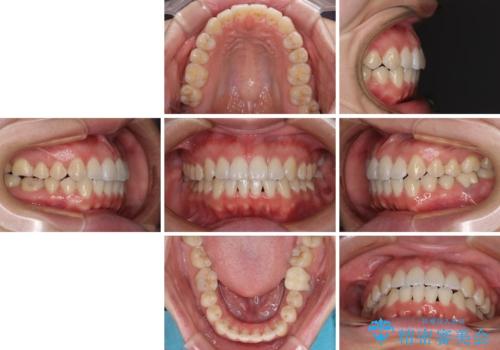

前歯のデコボコを治したい ワイヤー矯正

- 前歯のデコボコが気になるとのことで来院された患者様です。

目立たない装置と金属のワイヤーで矯正治療を行うこととしました。

1年半程度の期間を見込んでいましたが、上下の真ん中の位置をできる限り合わせるための調整に少し時間がかかってしまいました。

咬み合わせが安定し、前歯の汚れも付きにくくなりました。